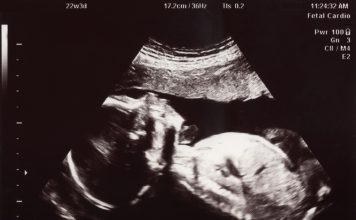

January 22: Day of Prayer for the Legal Protection of Unborn Children (links)

God our Creator, we give thanks to you, who alone have the power to impart the breath of life as you form each...